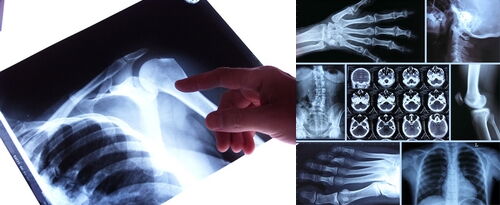

RÖNTGENDIAGNOSTIK

Mit dem bildgebenden Verfahren der Röntgenaufnahme steht uns zusätzlich ein probates, strahlungsarmes Verfahren zur Verfügung, mit dem krankhafte Veränderungen im Knochen sehr genau erfasst werden können.

Neben der konventionellen Röntgenaufnahme machen wir in unserer Orthopädischen Praxis bei bestimmten Krankheitsbildern zusätzlich sogenannte Funktionsaufnahmen, die uns Aufschluss über den Zustand der Wirbelsäule und bestimmter Gelenke in ihrer Bewegung geben.

Sollten diese beiden Methoden nicht ausreichen, werden wir nach Absprache mit dem Patienten Untersuchungsmethoden wie Computer- oder Kernspintomografie veranlassen.